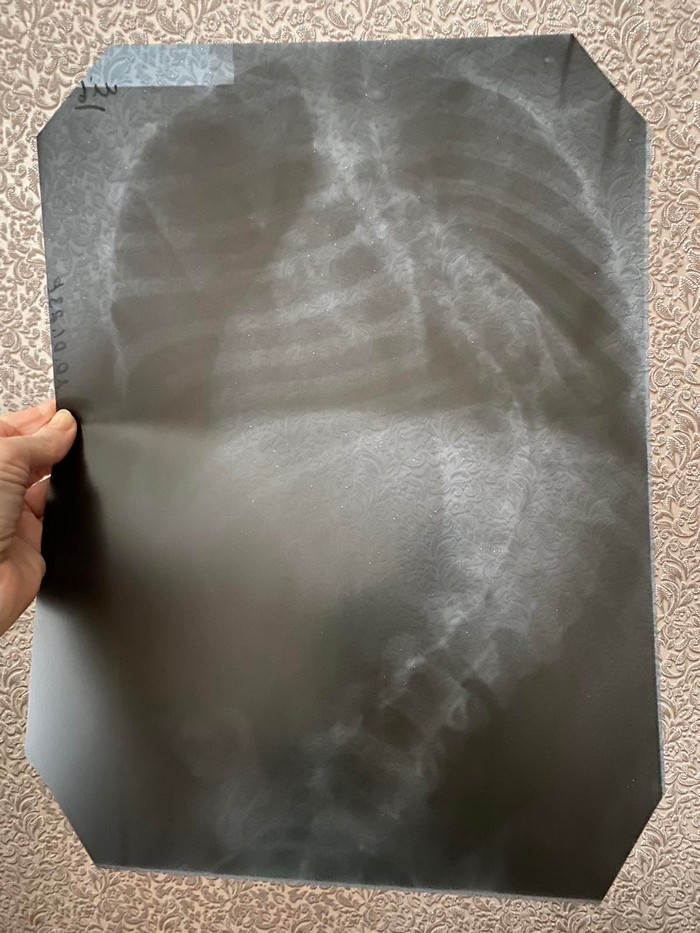

Але виявилось, що цього недостатньо. Вона росте. Анатомічно тіло не справляється з навантаженням. До паралічу додалося викривлення хребта. Воно прогресує. Під загрозою стало її подальше життя. Для стабілізації її стану потрібна госпіталізація та подальша надскладна операція. Проте вартість майбутнього лікування занадто висока – орієнтовано від 500 тисяч гривень.

Виписки із діагнозом на фото.